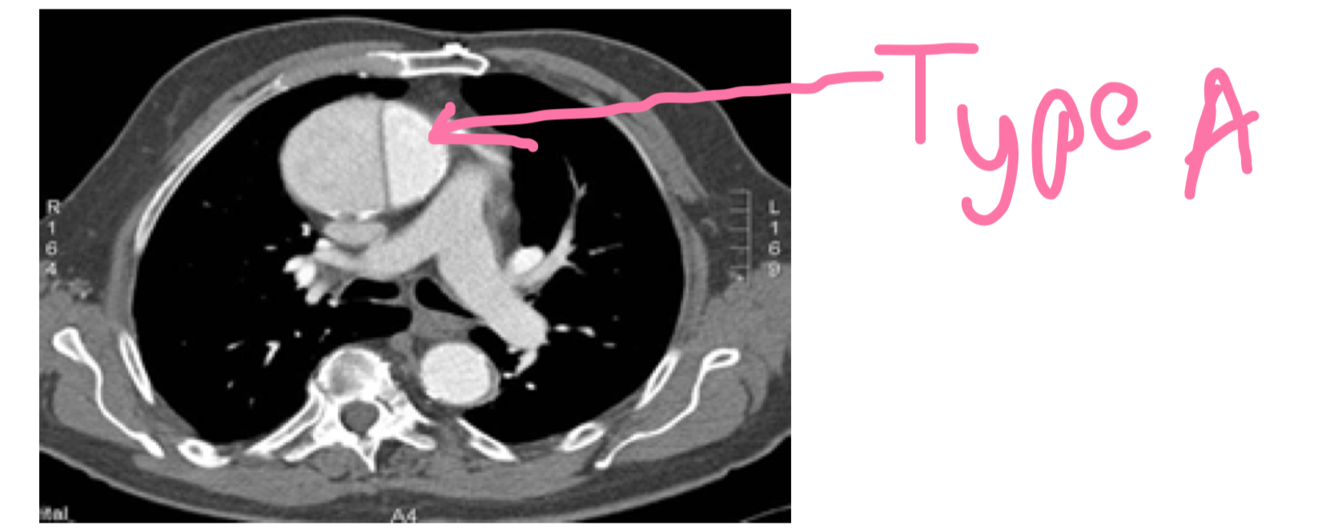

What can be seen on the CT thorax/aniogram in aortic dissection?

ordered as soon as suspected- include chest,abdo and pelvis to visualise the extent of aneurysm and to see if its suitable for an endo vascular repair

=> shows false lumen

Type A : Ascending aorta ( most common ) 70% - retrosternal chest pain